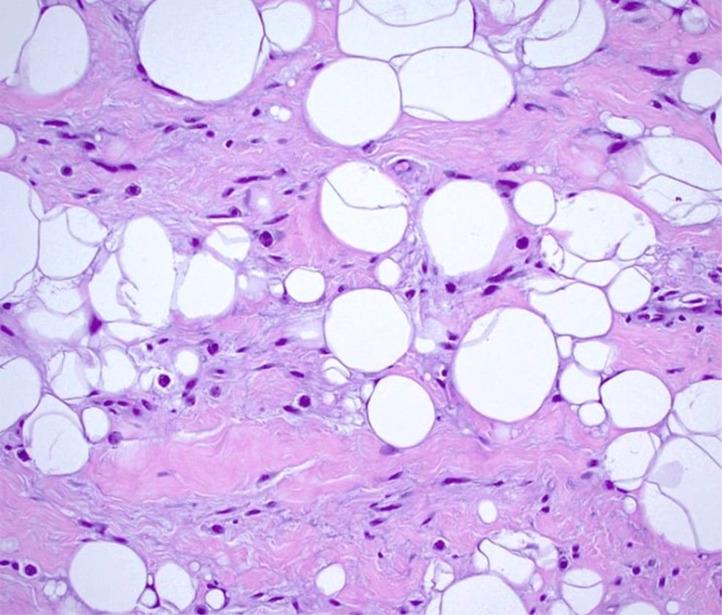

Spindle cell lipoma (SCL) represents an infrequent subtype of lipoma distinguished by its distinctive histopathological characteristics and tendency to localize in the subcutaneous tissues of the upper back, neck, and shoulder regions. In this report, we describe an unusual instance of SCL manifesting in the cervical area of a 62-year-old female individual. The patient exhibited a progressively enlarging painless mass situated in the left supraclavicular region for 8 years. Radiographic assessments disclosed a clearly demarcated, enclosed mass indicative of a lipomatous lesion. Microscopic analysis of the surgically removed specimen verified the presence of SCL, featuring mature adipocytes interspersed with spindle cells and collagen fibers. Subsequent immunohistochemical testing corroborated the diagnosis through the detection of CD34 positivity and S-100 protein negativity. Subsequent to surgical excision, the patient experienced an uneventful recovery period, devoid of any signs of recurrence throughout the monitoring phase. Despite its rarity, SCL should be contemplated in the differential diagnosis of neck masses, particularly when radiological findings point towards adipose tissue-related neoplasms. Timely identification and suitable intervention play a pivotal role in ensuring positive prognoses for individuals afflicted with SCL in the neck region.

梭形细胞脂肪瘤(SCL)是一种罕见的脂肪瘤亚型,其特征在于独特的组织病理学特征,并倾向于位于上背部、颈部和肩部区域的皮下组织中。在本报告中,我们描述了一例发生在一名62岁女性颈部区域的罕见SCL病例。患者左侧锁骨上区域出现一个逐渐增大的无痛性肿块,持续8年。影像学评估显示有一个边界清晰的包膜肿块,提示为脂肪瘤性病变。对手术切除标本的显微镜分析证实存在SCL,其特征为成熟脂肪细胞与梭形细胞和胶原纤维相间分布。随后的免疫组织化学检测通过检测CD34阳性和S-100蛋白阴性证实了诊断。手术切除后,患者恢复顺利,在整个监测期内无任何复发迹象。尽管SCL罕见,但在颈部肿块的鉴别诊断中应考虑到它,特别是当影像学表现指向脂肪组织相关肿瘤时。及时识别和适当干预对于确保颈部SCL患者的良好预后起着关键作用。